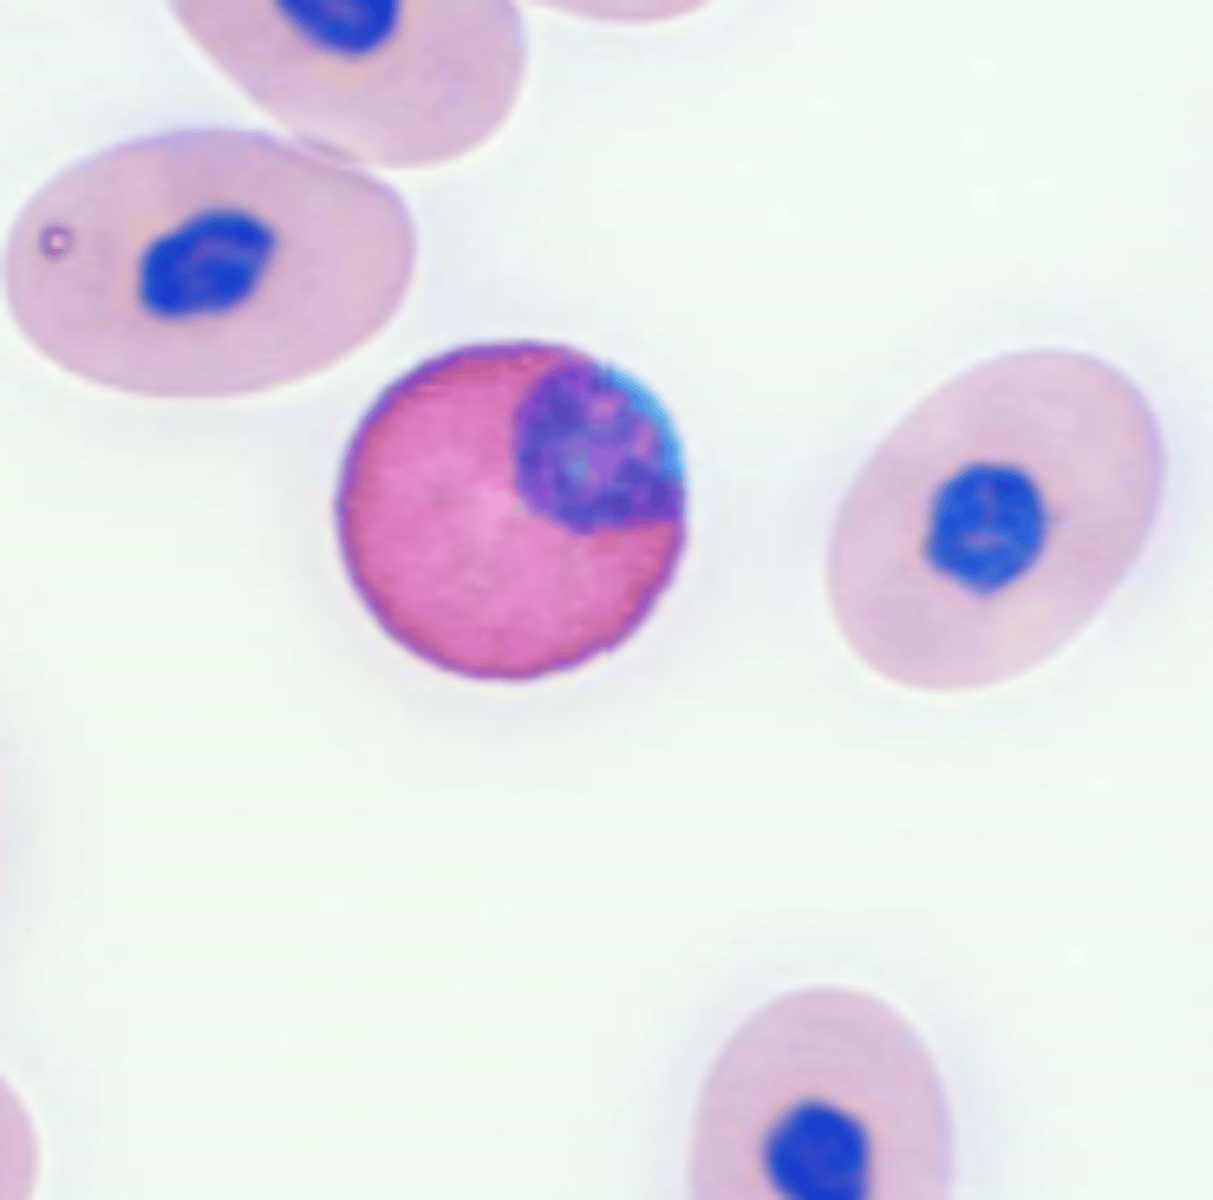

haemoproteus

exotic hemoparasite

nucleus is "embraced" not "displaced"

via blood sucking insects

plasmodium

exotic hemoparasite

causes avian malaria

via mosquitoes